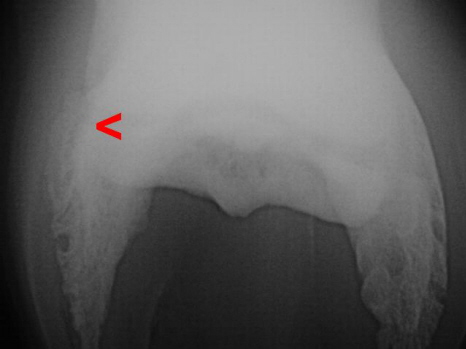

Hufbeinastfraktur